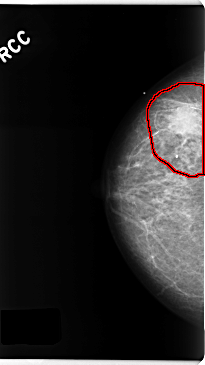

FILE: C_0195_1.RIGHT_CC.OVERLAY

TOTAL_ABNORMALITIES 1

ABNORMALITY 1

LESION_TYPE MASS SHAPE ROUND MARGINS ILL_DEFINED

ASSESSMENT 5

SUBTLETY 5

PATHOLOGY MALIGNANT

TOTAL_OUTLINES 1

BOUNDARY